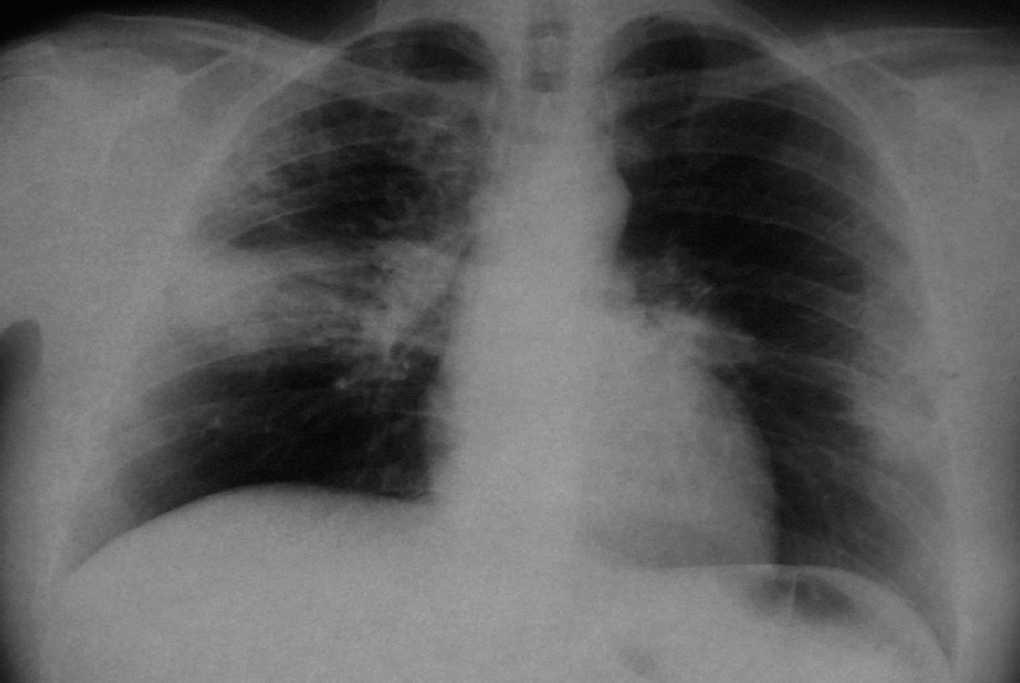

The patient brought a chest X-ray performed in February 2002 showing a bilateral alveolar pattern (fig. 1) and a chest computed tomography scan (fig. 2) taken during the period in which he had acute symptoms. There was consolidation of the left inferior lobes and right middle lobe. Laboratory analyses showed leukocytes 12300 mm 3 (eosinophils 33 %), platelets 576000 mm 3, globular sedimentation rate 105 mm/h, glucose 111 mg/dl and creatinine 0.9 mg/dl.

Figure 2.--CHEST CT SCAN 2002: consolidation area in both inferior lobes and middle lobe with some areas of bronchogram in its interior. Some lymph node abnormalities of significant size in mediastinum.

Chest X-rays were repeated in October 2003 and March 2004, showing disappearance of the acute infiltrates.